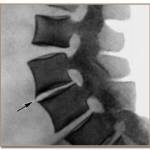

Для миеломной болезни характерны: мучительная боль в костях, патологические переломы, компрессионные переломы позвонков (хр радикулиты, сдавление спинного мозга), гиперкальциемия.

- Миеломная болезнь. Характеризуется болью в костях позвоночника, ребрах и тазе. Повышается хрупкость костей. Основное осложнение: компрессионный перелом позвоночника с ущемлением нервных отростков.